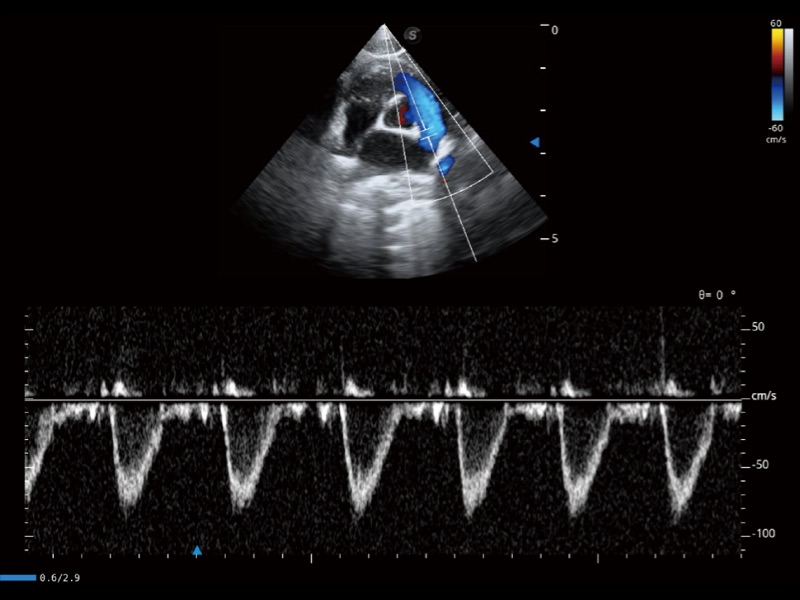

通過(guò)創(chuàng)新的 Matrix E自適應(yīng)濾波器和超長(zhǎng)時(shí)間域算法,極大提升超低速微細(xì)血流的檢出能力,同時(shí)更精準(zhǔn)地濾除軟組織和噪聲信號(hào),為獸用醫(yī)生提供以往無(wú)法通過(guò)常規(guī)血流獲得的疾病診斷信息。

通過(guò)色彩血流和實(shí)時(shí)寬景相結(jié)合,可觀察到完整的靜脈或動(dòng)脈的血流,方便醫(yī)生檢查。實(shí)時(shí)掃查過(guò)程中,如有任何操作失誤也可以很容易地進(jìn)行回掃擦除,而不會(huì)中斷掃查。

實(shí)時(shí)用顏色表示心肌組織運(yùn)動(dòng),觀察和定量組織的運(yùn)動(dòng)情況,對(duì)快速檢測(cè)與評(píng)估心肌的灌注和活性、電傳導(dǎo)及心肌收縮和舒張功能等均能提供重要的診斷信息。